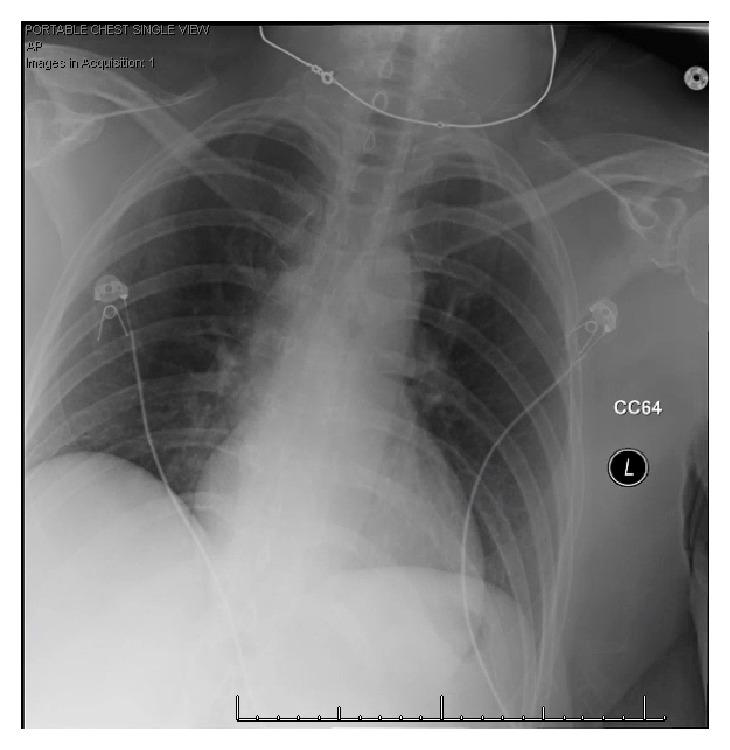

A Fatal Case of Influenza B Myocarditis with Cardiac Tamponade.

We present a case of cardiac tamponade in the setting of influenza B infection in a previously healthy 57-year-old woman, with progression to refractory shock and death. Autopsy revealed myocardial necrosis with infiltration of CD3+ lymphocytes, and little evidence of viral pneumonia.